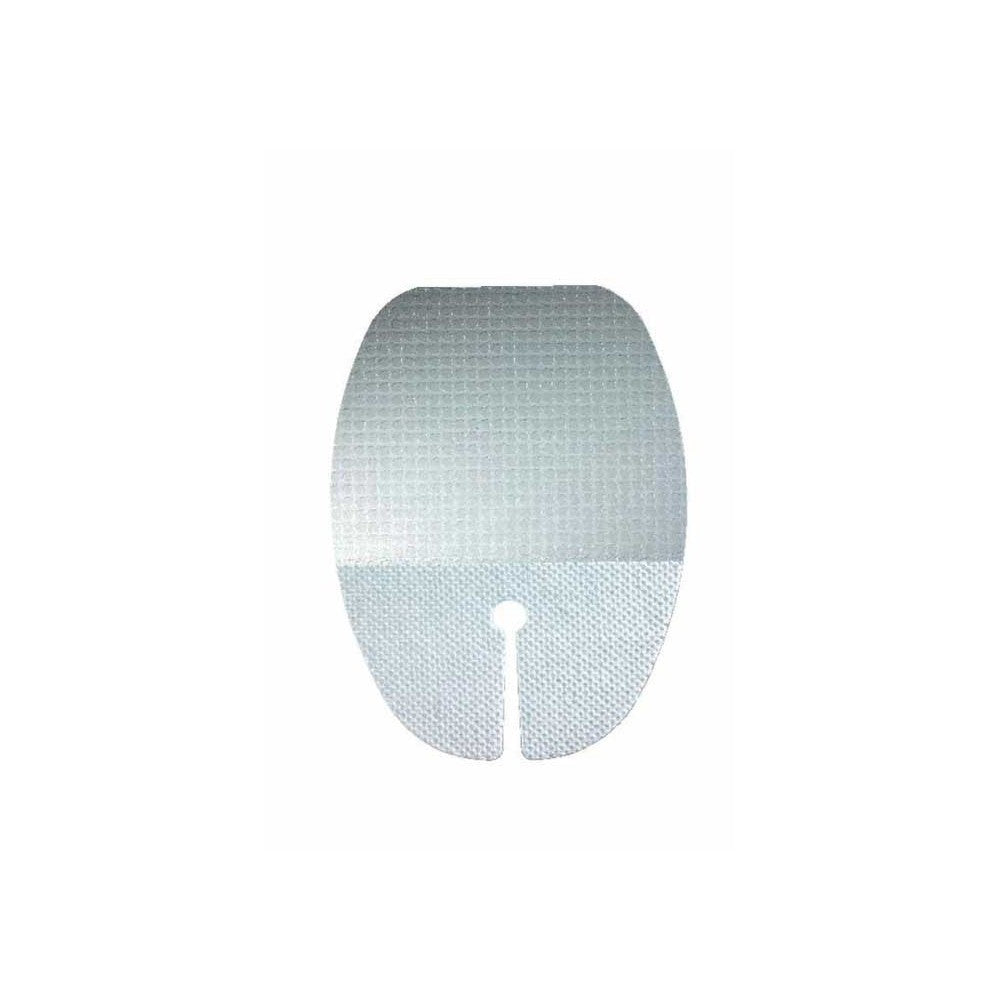

IV3000 1-HAND™

Film transparent avec réaction à l’humidité

Spécialement conçu pour répondre aux besoins des professionnels en matière de fixation de cathéters et de protection des sites intraveineux.